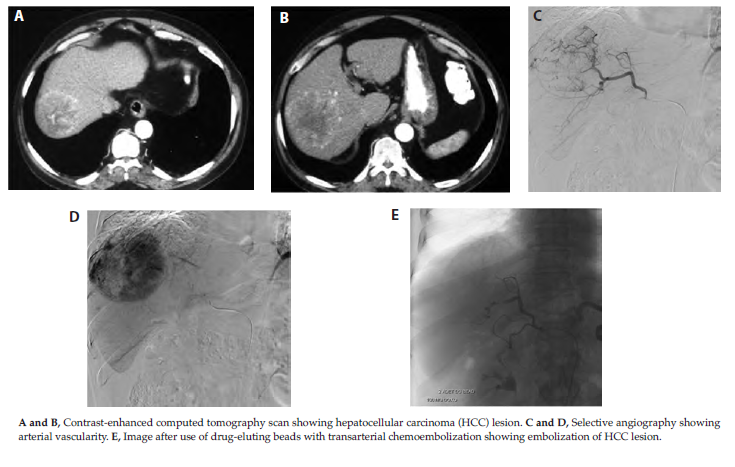

A number of factors have been correlated with effective post-TACE response. These include tumor diameter < 5 cm, < 50% replacement of liver by tumor tissue, and unilobar tumor. Other prognostic factors include the alpha-fetoprotein level, differentiation of HCC, number of tumor nodules, portal vein thrombosis, presence of tumor capsule, and degree of lipiodol retention postprocedure.5,10,15 Drug-eluting beads are microspheres that can be loaded with chemotherapeutic agents and used for TACE. Drug-eluting beads produce controlled, sustained release of chemotherapy at decreased peak plasma levels within the systemic circulation (Figure 3). A randomized clinical trial among 212 patients with intermediate-stage HCC found that TACE with drug-eluting beads resulted in similar response rates to conventional TACE (27% vs 22% complete response and 25% vs 21% partial response) and similar treatment-related serious adverse effects.16

Figure 4. Hypervascular Multiple Hepatocellular Carcinoma Lesions in the Right Lobe of Liver

Figure 5. Computed Tomography Showing Hypervascular Irregular and Large Hepatocellular Carcinoma Lesion (top panels) and Stable Lesion for 2 Years After 1 Session of Chemoembolization and Radioembolization (bottom panels)